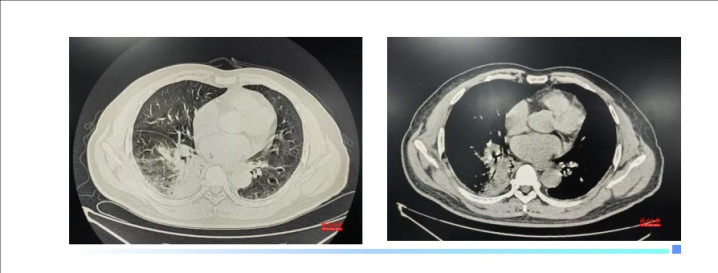

“会不会是鼠咬热?”林秀华心里打了个问号。但王人集患者的肺部CT透露右下肺炎症,以及恒久战斗家禽的履历,她怀疑可能另有“真凶”。

最终确诊为鹦鹉热衣原体肺炎

吴先生入院工夫就先后出现了肝挫伤、肺炎加剧。“幸而会诊明确后立即和洽了和洽决策,两周后,吴先生病情安宁好转了。”林秀华主任先容,鹦鹉热若是会诊实时、和洽范例,预后一般邃密;但若是延误和洽,病死率可达15%~20%。